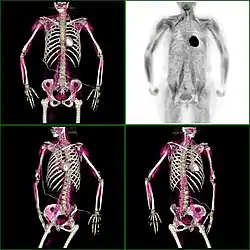

Knochenmetastasen

Knochenmetastasen unterschiedlicher Tumorerkrankungen können mit PET/CT sehr gut nachgewiesen werden. Das Verfahren ist sensitiver als die SPECT und erheblich sensitiver als die planare Skelettszintigrafie, jedoch auch aufwändiger und somit teurer. Je nach Tumorentität werden unterschiedliche Tracer verwendet, meist jedoch FDG und Natriumfluorid, beim Prostatakrebs auch 11C- oder 18F-Cholin. Metabolische Aktivität des Tumors ist mit Hilfe des Tracers FDG, die Reaktion des Knochens auf den Tumor mit der Natriumfluorid-PET/CT meist gut darstellbar (siehe Bildbeispiele).[33]

-

HDP-Skelettszintigramm eines Patienten mit Nierenkrebs: Die Knochenmetastasen im Halswirbelkörper 7 und in der Lendenwirbelsäule (LWK 1&2) sind aufgrund der geringen Auflösung der planaren Skelettszintigrafie nur zu erahnen. -

SPECT-Aufnahme des HDP Skelettszintigramms desselben Patienten; von den beiden Metastasen in der Lendenwirbelsäule ist nur eine einzige Läsion erkennbar; die Läsion in der Halswirbelsäule ist nicht dargestellt. -

FDG-PET desselben Patienten: Die osteolytische Knochenmetastase im Halswirbelkörper reichert FDG nicht an und ist nur im CT erkennbar. Die beiden weiteren Knochenmetastasen in der Lendenwirbelsäule werden dagegen auch in der FDG-PET/CT dargestellt. -

Natriumfluorid-PET/CT desselben Patienten: Die osteolytische Knochenmetastase in der Halswirbelsäule zeigt einen extremen Uptake und ist klar erkennbar. Die beiden weiteren Knochenmetastasen in der Lendenwirbelsäule stellen sich in der PET/CT-Aufnahme ebenfalls sehr gut dar. -

Vergleich derselben Läsion des vorgenannten Patienten: Die FDG-PET/CT-Aufnahme zeigt die Stoffwechselaktivität des Tumors. -

Vergleich ein und derselben Läsion des vorgenannten Patienten: Die Natriumfluorid-PET/CT-Aufnahme zeigt die Stoffwechselaktivität des Knochens als Reaktion auf den Tumor.